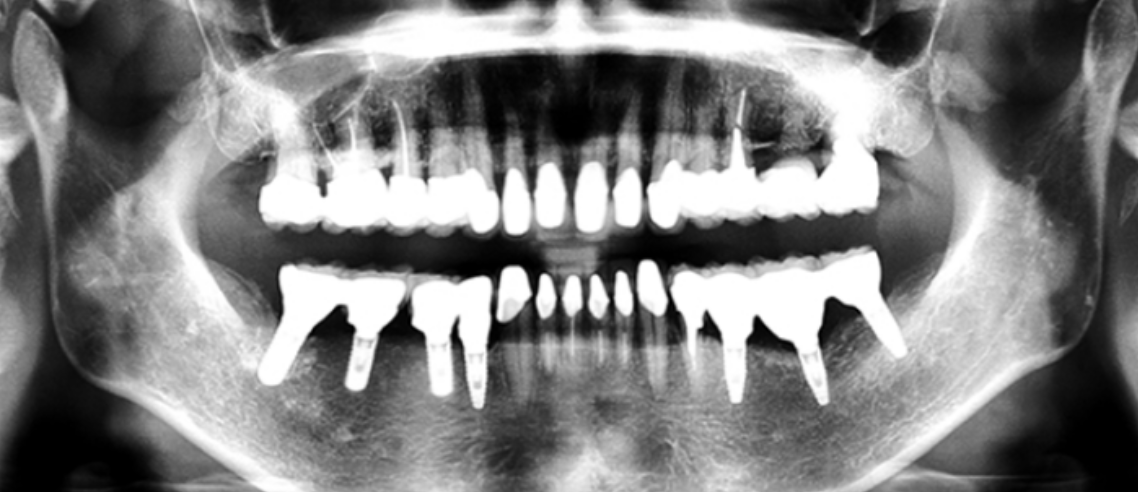

下の奥歯が左右なくなっており、かみ合わせが深くなっています。

顎のずれは認めませんが、歯肉が厚く中に炎症を取りこみやすいタイプの歯肉です。

左の顎の骨が大きく溶けてなくなっております。

かみ合わせの深さを改善し、左下の骨を作り人工歯根で再構築しました。